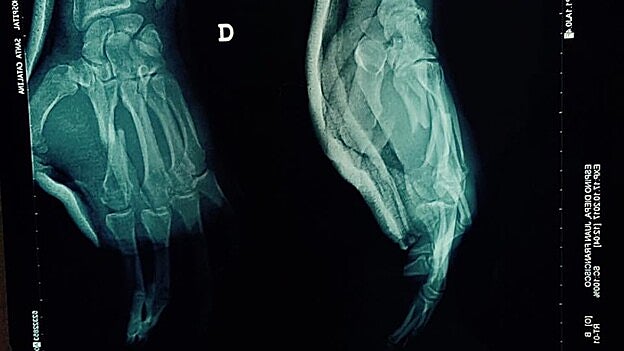

Juan Espino, El Trota, dice adiós a la competición oficial en 2017. El peleador grancanario, que a pesar de la lesión se impuso al austríaco Martin Buday el pasado sábado, pasará este miércoles por el quirófano por la fractura del quinto metacarpiano de la mano derecha. «Esta lesión, que es habitual entre los profesionales de las artes marciales mixtas, trastoca totalmente mis planes y frena mi trayectoria. No podré pelear más en dos meses, por lo que tendré que suspender todos los compromisos que tenía hasta final de año», aseveró resignado a CANARIAS7, pero al tiempo satisfecho por los éxitos logrados durante los últimos meses. «Son cosas que suceden. No podré golpear con la mano derecha en 6 u 8 semanas, pero seguiré preparándome y perfeccionando otras cosas para volver al máximo a comienzos del próximo año. Tengo un balance de 8/1 y una posición envidiable a nivel mundial, lo que me hace seguir con ganas mi preparación. Así que en 2018 prepárense que volveré con más ganas aún», prometió en sus redes sociales después de confirmarse su período de baja.

Imagen de la mano dañada. / C7

El Trota se impuso al austriaco Martin Buday en la velada del pasado sábado en la velada de artes marciales mixtas disputada en Tenerife. El grancanario venció a los puntos a un rival «muy duro», con la dificultad añadida de que se rompió el quinto metacarpiano de la mano derecha en el primer asalto. «Tuve que hacer una pelea diferente, con desplazamientos, paladas y trabajo en el suelo», dijo el grancanario, que no esperaba que la lesión tuviese tanto alcance. «Pude seguir, con dolor, la pelea y sabía que tendría que parar por la mano, pero no esperaba que fuese para tanto. Me han asegurado que la intervención es sencilla y que tendré una buena recuperación», afirma optimista.